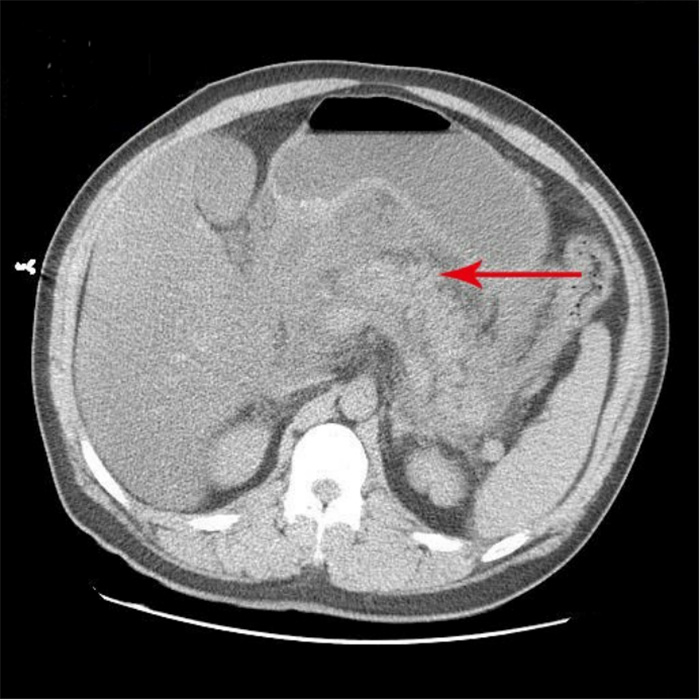

1 资料与方法患者吴某,男,33岁,身体质量指数37 kg/m2,因“腹痛13 h”急诊就诊。患者餐后出现上腹部持续性胀痛,向腰部放射,疼痛逐渐加重,急诊收住院。既往史:高血压病史2年,血压最高达200/100 mmHg(1 mmHg=0.133 kPa),未服用降压药。糖尿病病史1年,未行治疗。查体:体温36.6 ℃、脉搏130次/min、呼吸38次/min、血压228/113 mmHg,神志清楚,皮肤、巩膜无黄染,两肺未及干湿性啰音;心律齐,未闻及杂音,腹膨隆,腹肌紧张,上腹部压痛明显,无反跳痛,肠鸣音弱;肌力、肌张力正常,神经系统检查阴性。主动脉CTA:未见夹层;上腹部CT:AP(见图 1);心电图:窦性心动过速;肝胆脾彩超:重度脂肪肝,胆囊饱满,胰腺肿大并不均质改变。化验检查示,随机血糖32.8 mmol/L,动脉血气分析pH 7.313,二氧化碳分压23.8 mmHg,氧分压68.7 mmHg,标准碳酸氢根11.8 mmol/L,血氧饱和度93.5%,剩余碱-12.28 mmol/L(鼻导管吸氧FiO2 0.33),血乳酸12.6 mmol/l,总胆固醇12.61 mmol/L,甘油三酯23.31 mmol/L。血清钙1.56 mmol/L,凝血功能正常。血常规检查示,白细胞计数(WBC)14.08×109/L,中性粒细胞百分比(NE%)84.4%,红细胞数(RBC)5.73×1012/L,血红蛋白(HGB)194 g/L,红细胞压积(HCT)0.58,血小板数(PLT)410×109/L。肝功能检查示,丙氨酸氨基转移酶(ALT)、天冬氨酸氨基转移酶(AST)、r-谷氨酰转移酶(r-GT)、总胆红素(TBiL)、非结合胆红素(NCBiL)、结合胆红素(CBiL)均正常,总蛋白(TP)143 g/L,白蛋白(Alb)37.5 g/L。肾功能检查示,尿素氮(BUN)7.35 mmol/L,肌酐(Cr)296.8 μmol/L。尿液分析示,蛋白(Pro)3+,葡萄糖4+,酮体弱阳性,糖化血红蛋白9.3%,血淀粉酶2 320 U/L,尿淀粉酶22 073 U/L,脂肪酶382.80 mmol/L。患者入住急诊监护室8 h后胸闷、呼吸困难进行性加重,氧合指数 < 100,紧急行气管插管呼吸机辅助呼吸。

| 胰腺弥漫性增大,密度不均匀减低,周围间隙模糊并多发片絮状、索条状渗出影,胆囊不大,囊内未见明显异常密度影。 图 1 患者入院时腹部CT |